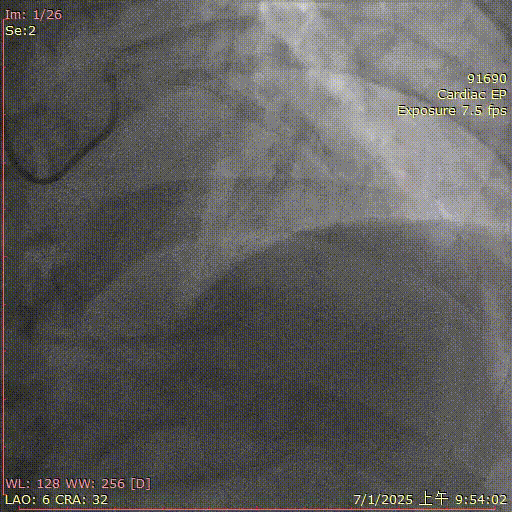

聂斌教授团队

基本情况:患者,男,75岁,因“呼吸困难伴胸闷3月”入院。

简要病史:2025年2月冠脉造影见前降支近段闭塞,见钝缘支侧枝供应,回旋支狭窄50%,右冠远段局限性狭窄80%,正向微导管支撑下尝试XT-A→G3→CP 12进入远段内膜下,双腔微导管支撑下未能调整至真腔,启动逆向尝试Sion→XT-A→SUOH 03未能通过钝缘支侧枝。J-CTO评分4

辅助检查:LVEF 60%,肌酐 127μmol/L

术前诊断:冠状动脉粥样硬化性心脏病,冠状动脉支架植入术后状态,心功能NYHA Ⅱ级,慢性阻塞性肺病,慢性肾脏病3期,脑梗史

术前造影